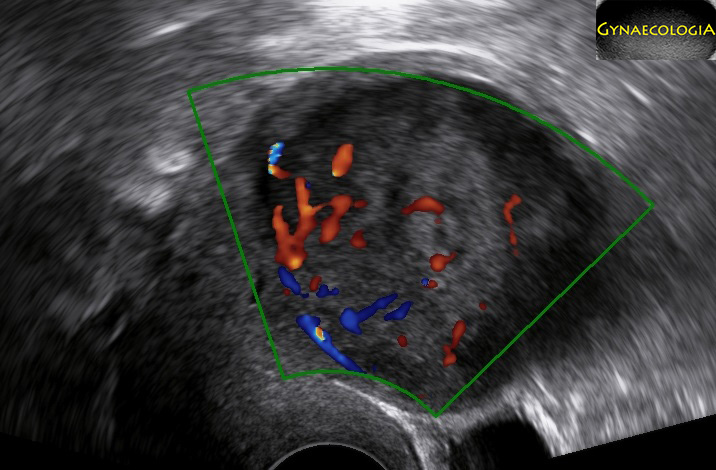

Ultrasound and MRI have been used extensively in an effort to distinguish among leiomyomata, leiomyosarcomata and even STUMP. Understanding the pathology behind these conditions, it shouldn’t come as a surprise that there is difficulty in setting pathognomonic features for each one (Oh, J., et al, 2019).

The following chart may be helpful when trying to establish a differential diagnosis:

| Leiomyoma | STUMP | Sarcoma | |

|---|---|---|---|

| Size | Variable | Variable | Usually already large when found |

| Borders | Regular | Regular | Could be irregular |

| Echogenicity | Isoechogenic or mixed | Isoechogenic or mixed | Inhomogenous |

| Calcifications | May appear | Absent | |

| Acoustic Shadows | Variable | Absent | Absent |

| Gynecological symptoms | May appear | Usually yes | Usually yes |

| Anechogenic areas | May appear | Yes | Yes, irregular |

| Vascularization | Circumferential and may even be intralesional | Circumferential and intralesional | Circumferential and intralesional |

| (Woźniak, A., & Woźniak, S., 2017) | (Cotrino, I., et al, 2020) | (Ludovisi, M., et al, 2019) |